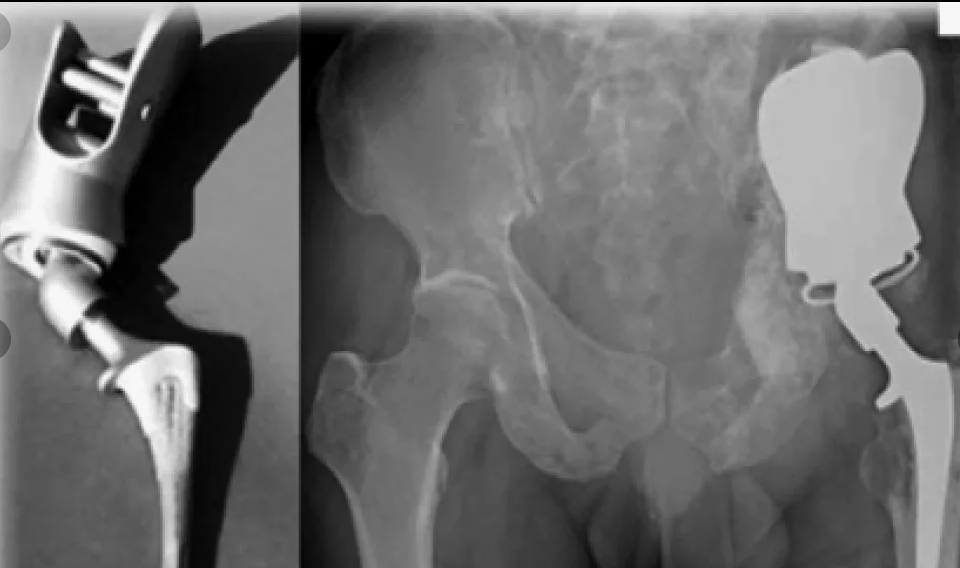

Шейка таза перелом

Шейка таза перелом 111 фото